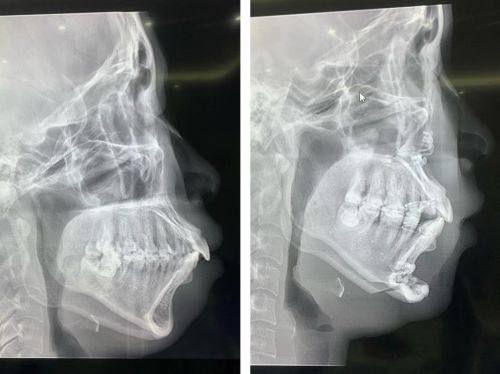

1. 凸嘴矫正:凸嘴会影响面部的整体美观,给人一种不和谐的感觉。尹泰镐院长在凸嘴矫正方面有着丰富的经验。他会根据患者凸嘴的具体情况,采用合适的矫正方法。对于一些轻微的凸嘴,可能会通过牙齿矫正来改善;而对于比较重度的凸嘴,可能会结合手术进行矫正。他会在术前进行详细的检查和评估,制定出更适合患者的治疗方案,让患者的面部轮廓更加协调。

2. 地包天矫正:地包天不仅影响美观,还会影响口腔的正常功能。尹泰镐院长能够正确地判断地包天的类型和程度,然后采取相应的矫正措施。他可以通过佩戴矫正器或者进行手术等方式,帮助患者纠正地包天的问题,修复正常的咬合关系和面部形态。

在擅长技术方面,他对凸嘴、地包天、牙齿矫正、口腔修复等项目都有深入的研究和不错的技艺。他能够根据患者的具体情况,制定个性化的治疗方案,让患者获得理想的治疗成效。